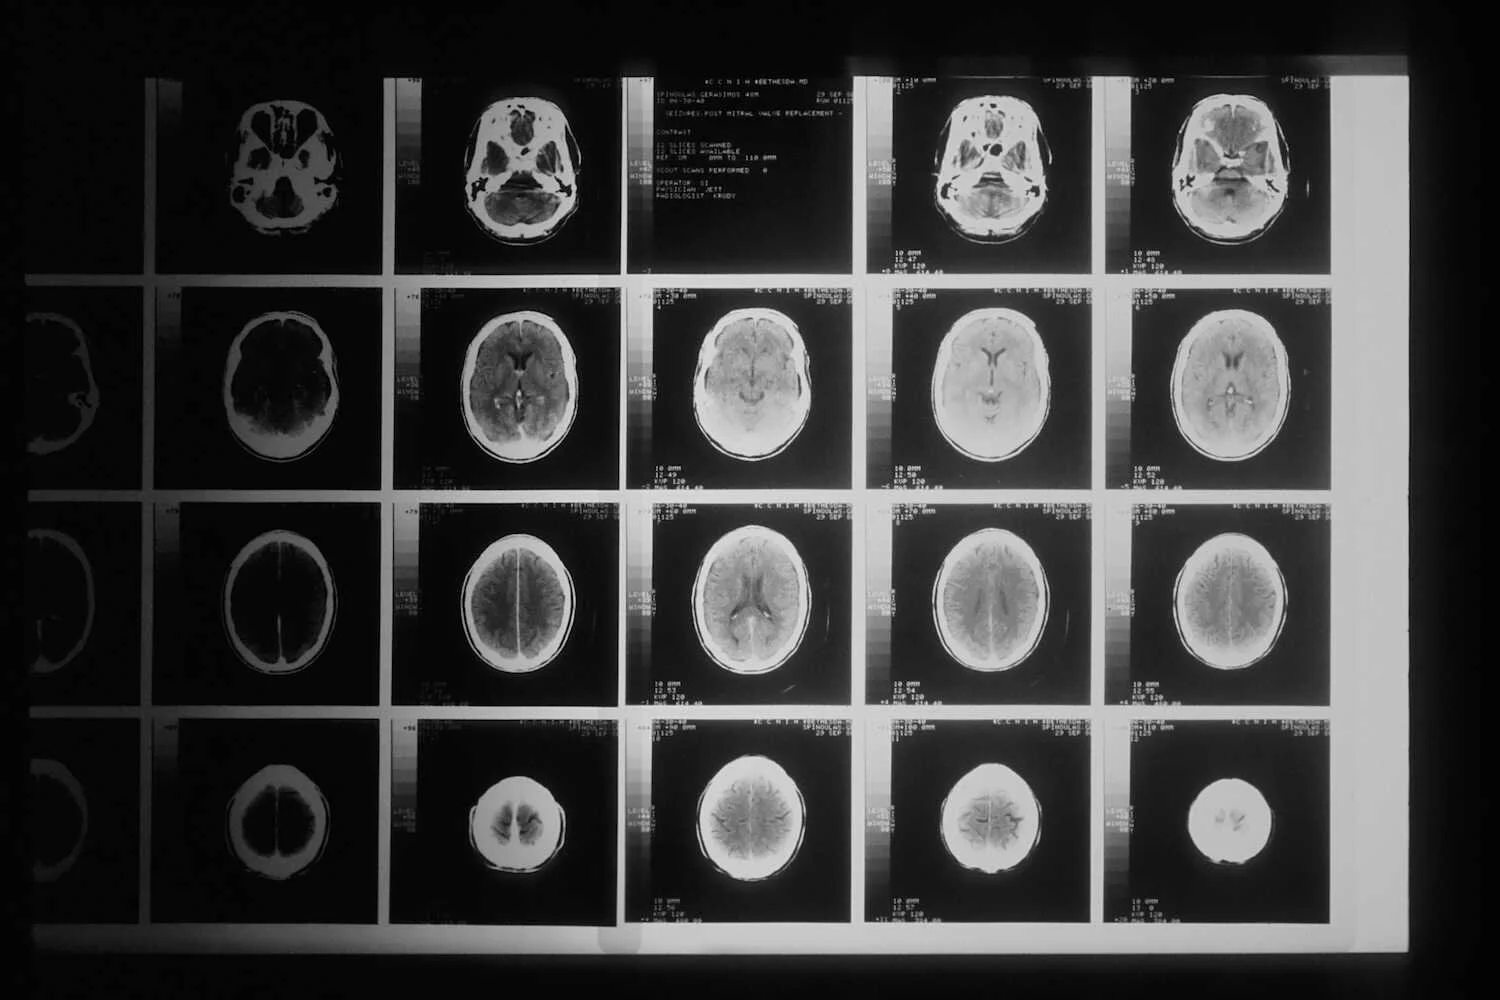

MRI is a primary tool for diagnosing brain tumors. It provides detailed images of the brain, helping identify the tumor's location, size, and characteristics.

• Computed Tomography (CT) Scan: CT scans may be used to detect and locate brain tumors, especially in emergencies when a rapid assessment is needed.